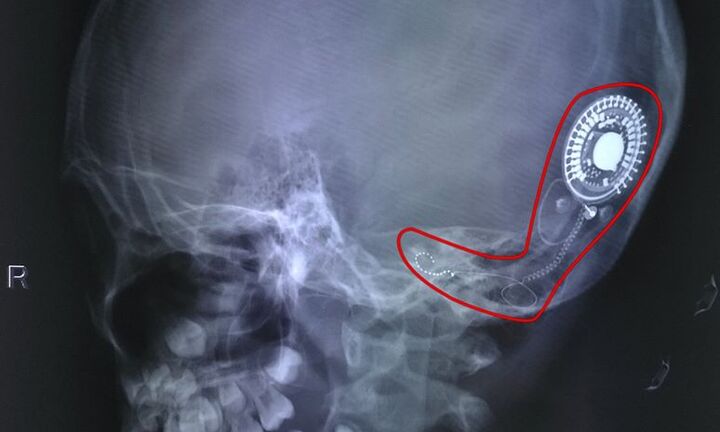

Lần đầu tiên được nghe tiếng thấy tiếng nói và âm thanh cuộc sống nhờ cấy điện cực ốc tai, cô bé 7 tuổi ở Đồng Nai khiến mọi người chứng kiến trào nước mắt vì xúc động.